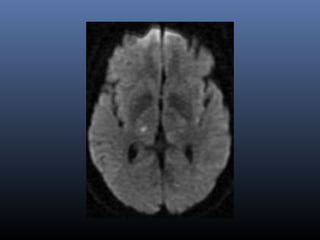

DWI

Most sensitive sequence in stroke imaging

High intensity in DWI indicate restriction of the

ability of water proton to diffuse extracellularly.

DWI- stroke

▪ Hyperacute stroke-Cytotoxic edema

▪ Lesion appears bright